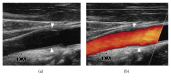

Idiopathic carotidynia (IC) is a rare and poorly understood syndrome consisting of unilateral neck pain, tenderness, and increased pulsations over the affected carotid bifurcation. A growing body of evidence supports the hypothesis that IC is a distinct clinicopathologic entity with characteristic imaging features. We report the case of a 34-year-old Caucasian male presenting with intense unilateral neck pain in the emergency setting. Computed tomography and ultrasonography revealed fusiform eccentric thickening of the ipsilateral carotid bifurcation without vessel narrowing. Contrast-enhanced magnetic resonance imaging depicted major perivascular enhancement without evidence of dissection. Further imaging and laboratory work-up excluded vasculitis. The diagnosis of IC was made. The patient was treated with nonsteroidal anti-inflammatory drugs and symptoms and imaging findings disappeared within a few weeks. Cross-sectional imaging allows not only ruling out IC mimickers but also making the correct diagnosis of this rare condition, in particular, as the clinical presentation of IC is often nonspecific.